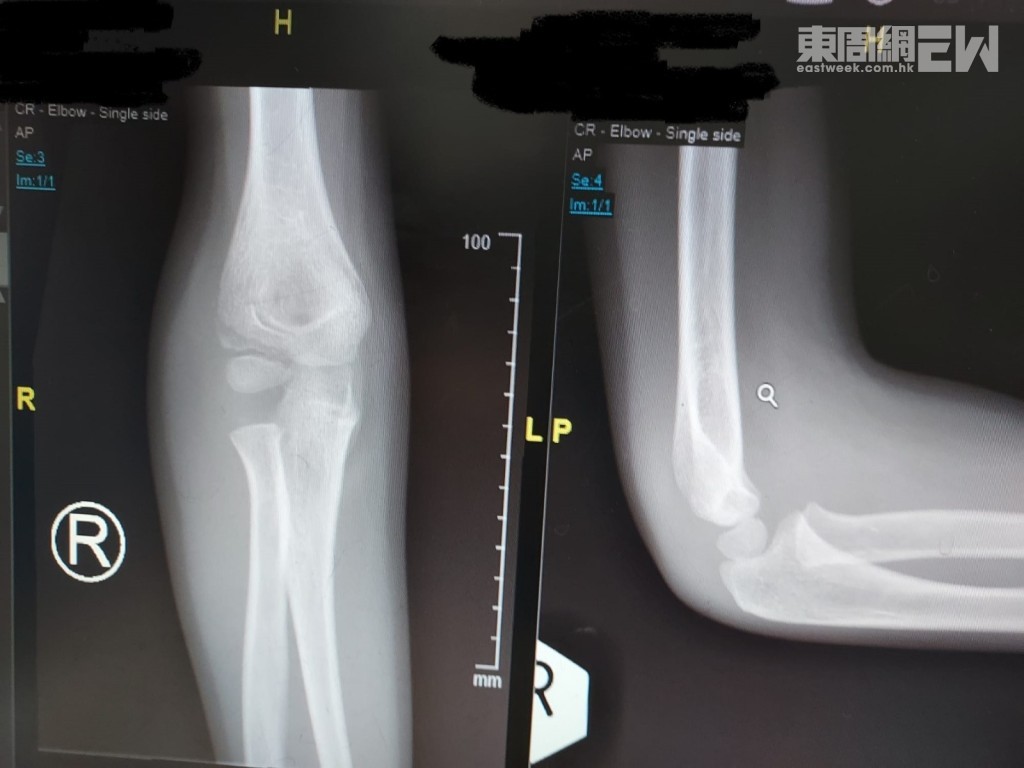

兒童骨裂(骨折)的X光檢查是診斷的主要且標準方法,能清楚顯示骨骼的形態、結構及連續性,並評估骨折的位置與嚴重程度。兒童骨骼兩端有生長板,X光上呈現細縫狀,容易與骨折混淆,因此有時需拍攝對側肢體X光片做比較以提高診斷準確性。

- 多角度拍攝:通常需同時拍攝多個角度(如正側位及斜位)以確保骨折不被忽略。

- 隱匿性骨折:部分微小或撕裂性骨折在初次X光難以發現,可能需7-10天後追蹤重拍X光,或使用MRI、核子醫學檢查等輔助診斷。